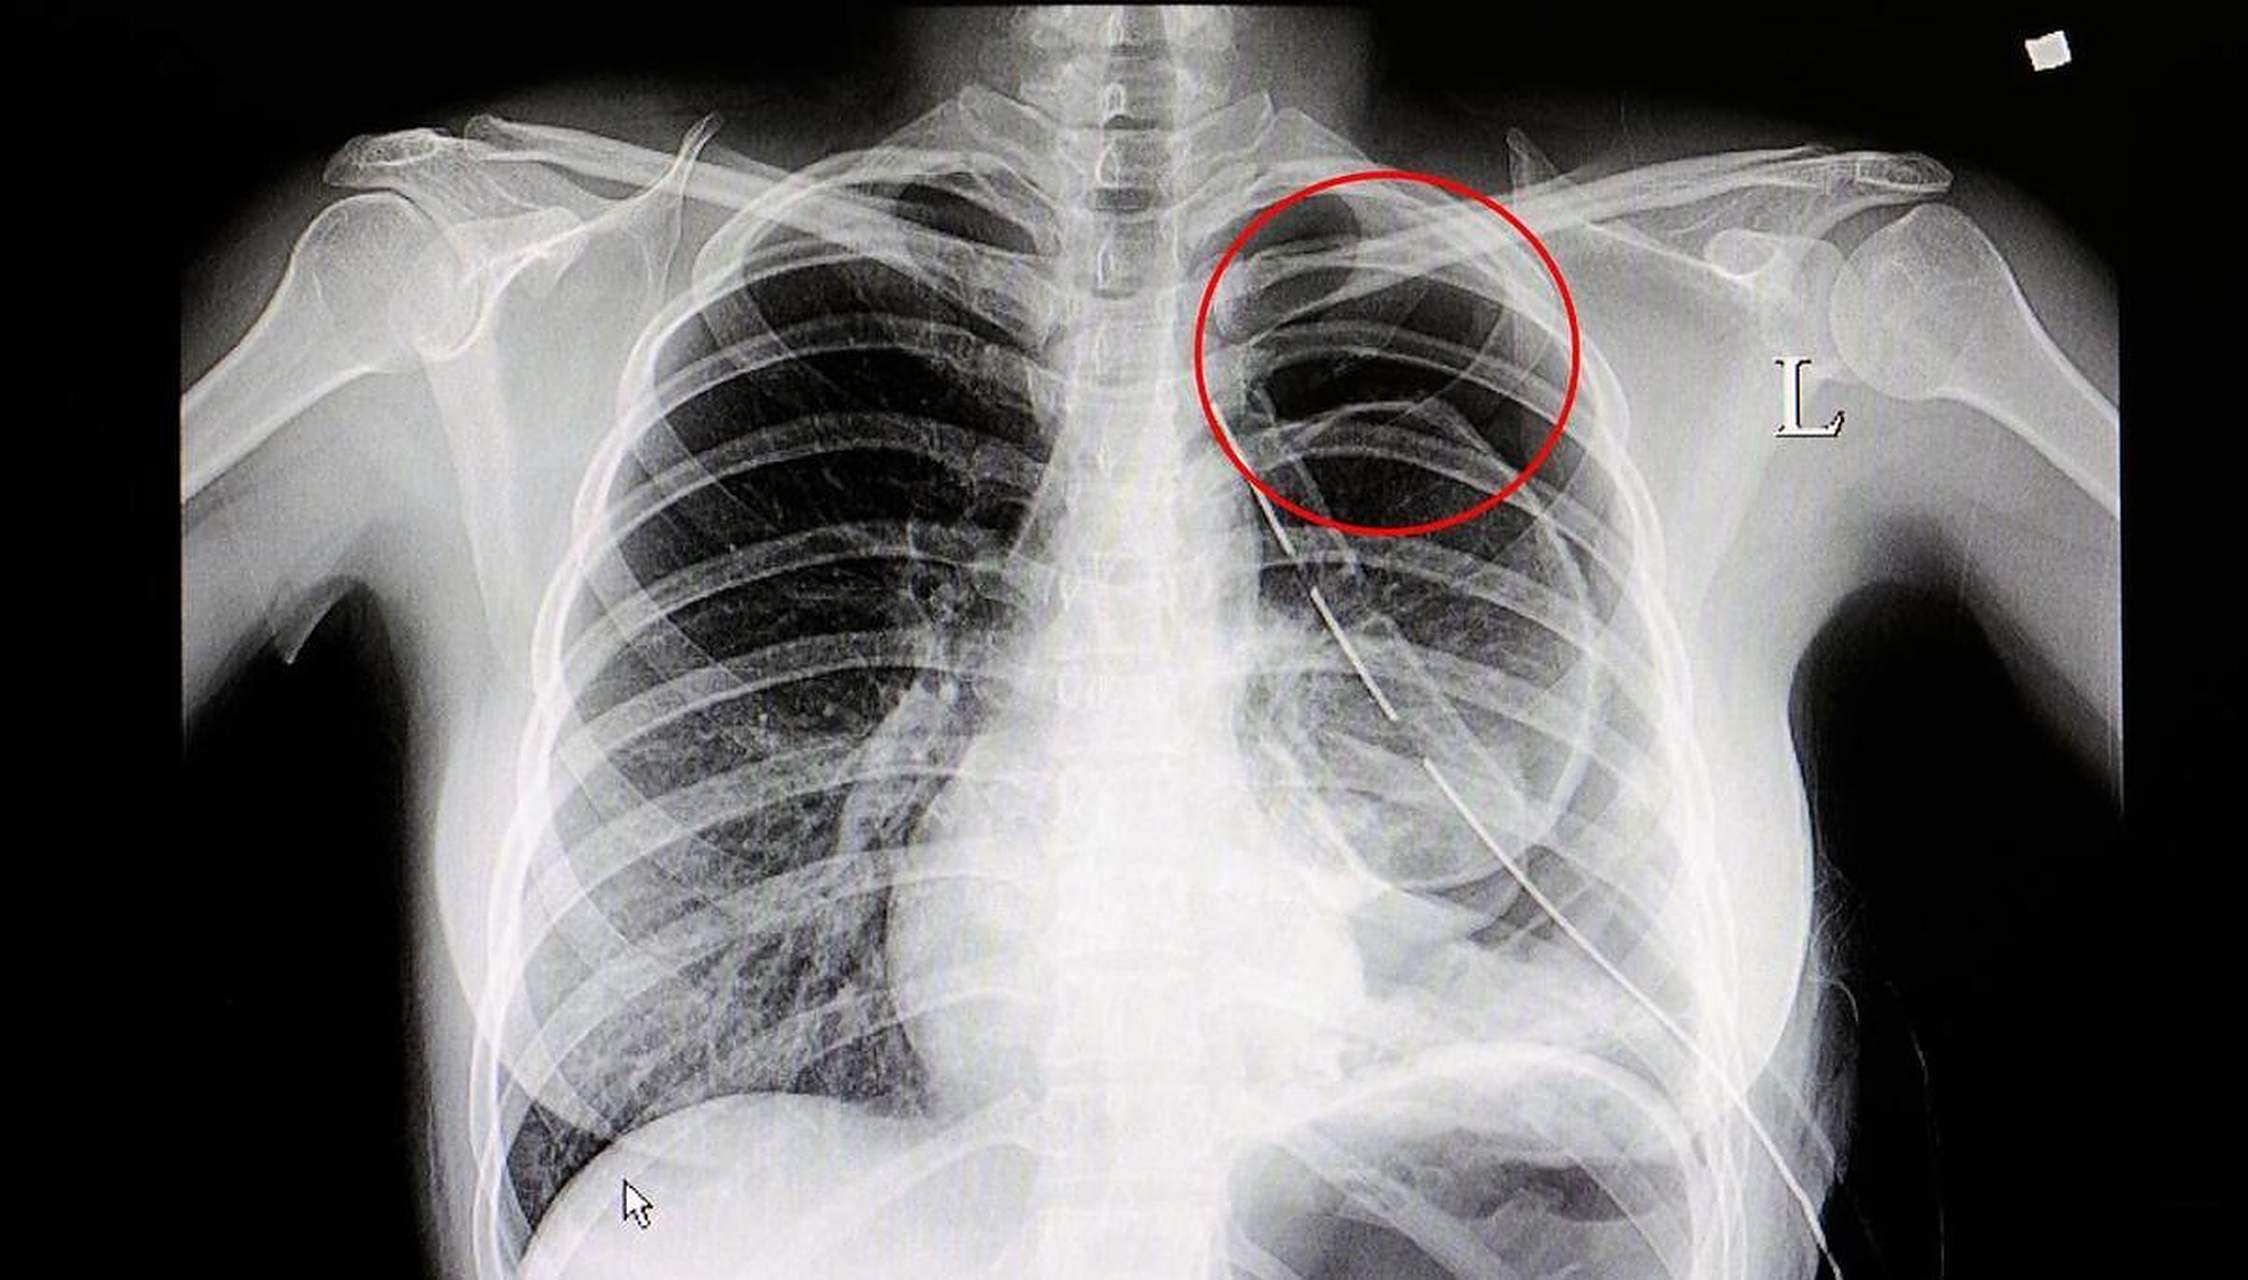

病例3:肺血基本正常,肺门影略大,双房影,心膈面延长.